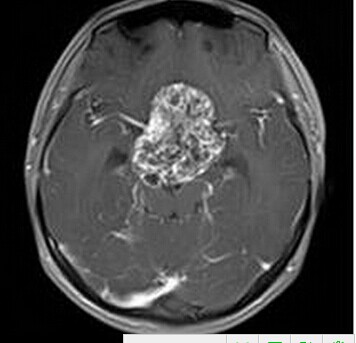

患者:男,15岁,双眼视力下降1年余,近来有嗜睡表现。

【正确答案】A 颅咽管瘤

根据肿瘤位于鞍区,且呈明显均匀强化,鉴别诊断还需要考虑鞍区毛细胞型星形细胞瘤。鉴别要点:

(1)多见于青少年;不规则分叶状肿块,边界清楚,体积较大;

(2)增强后明显均匀强化。

(1)颅咽管瘤的两个发病高峰年龄分别是4-15岁和35-45岁,其中实性颅咽管瘤多见于成年人,本例为青少年患者,发病年龄无特异性;

(2)对诊断有提示意义的征象是明显强化,内散在微囊状不强化区。